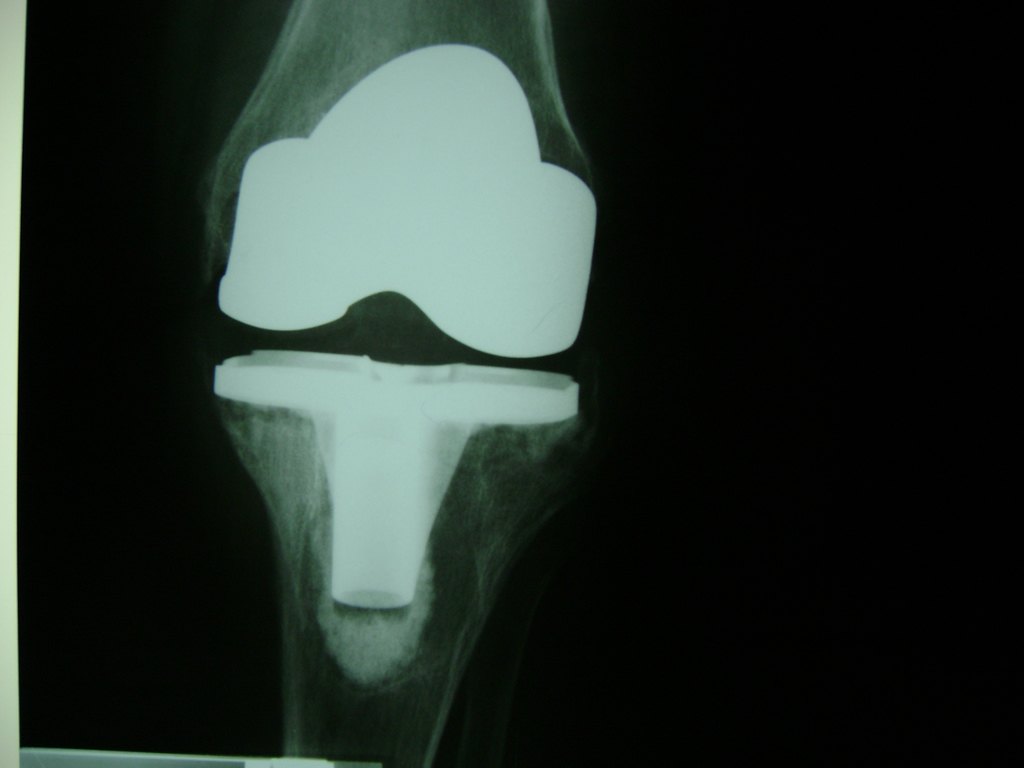

La artroscopia de rodilla es un cirugía en el cual la estructura interna de la articulación es examinada ya sea para realizar un diagnostico o para realizar un tratamiento, este procedimiento se realiza utilizando un instrumento parecido a un pequeño tubo llamado artroscopio.

La artroscopia se popularizo en 1960 y hoy en día es muy común en todo el mundo. Típicamente, es realizada por cirujanos ortopédicos de manera ambulatoria. Cuando se realiza de manera ambulatoria los pacientes pueden regresar a casa después de la operación, no se requiere quedarse en hospital.